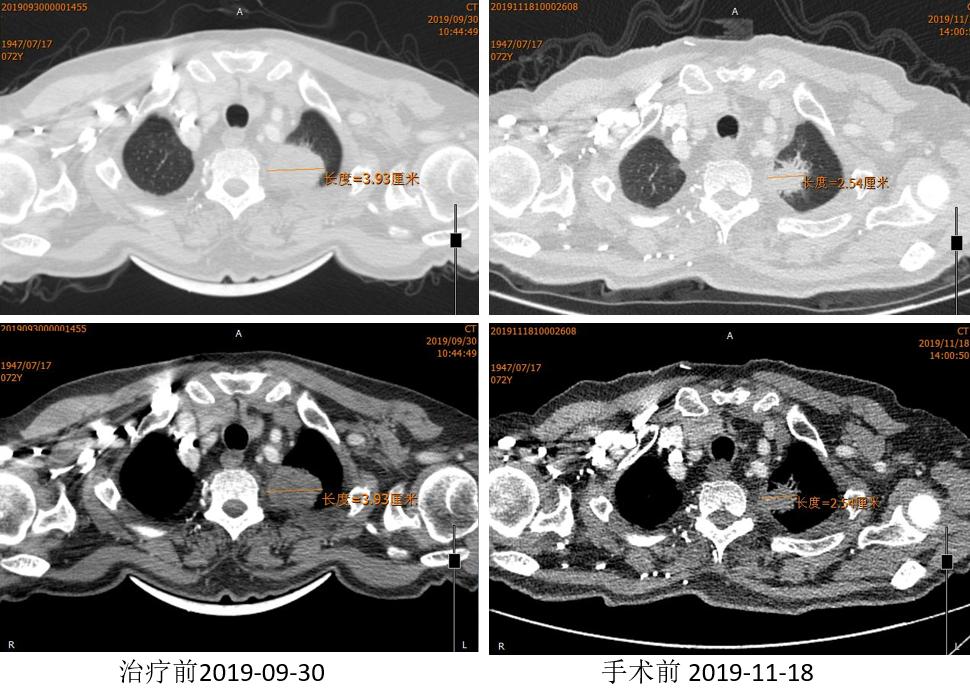

外周淋巴结CT

2019.12.03 行“VATS辅助切口左肺上叶袖式切除术”。